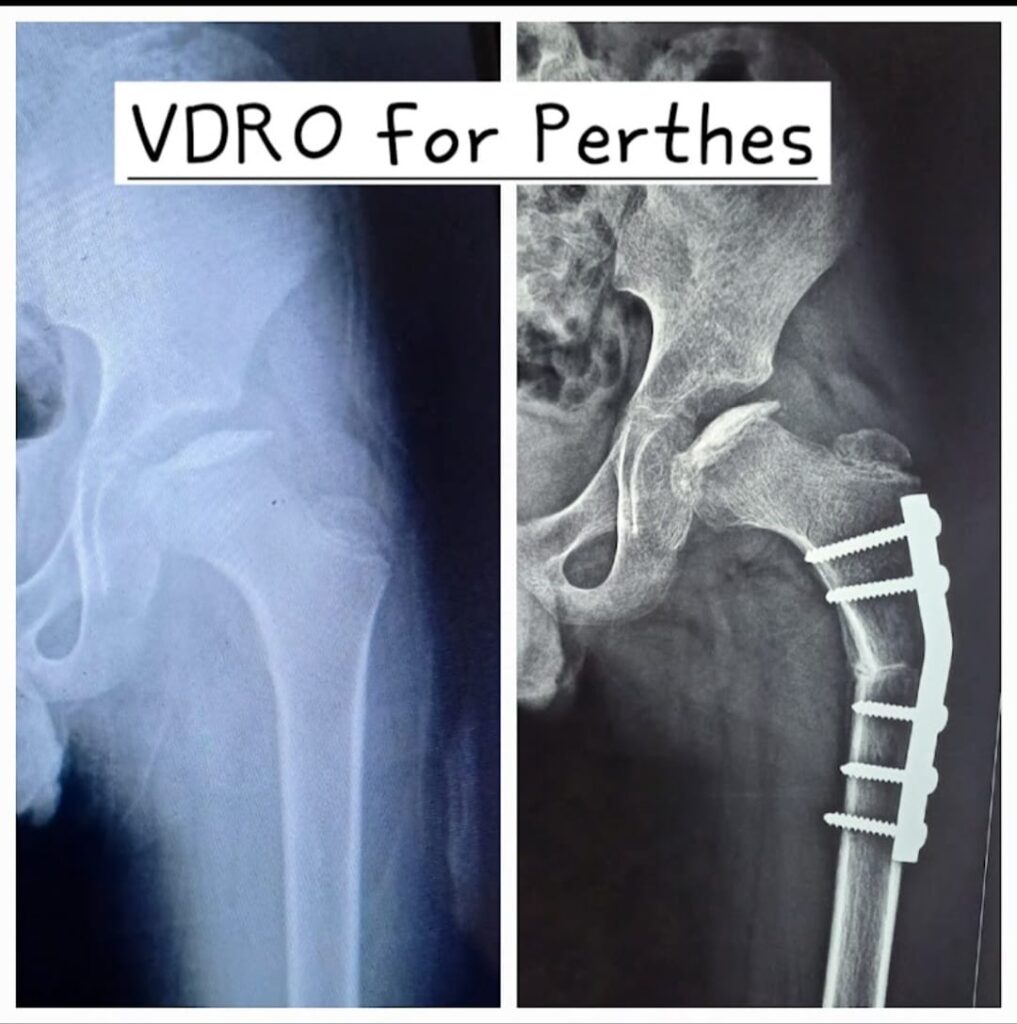

VDRO for Perthes